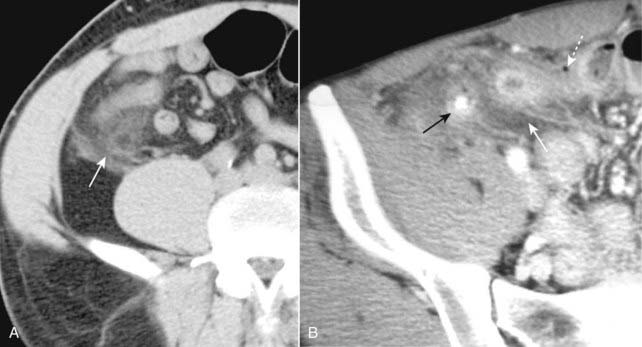

image CT evaluation of liver masses is usually done with a combination of scans obtained before and after intravenous contrast injection. Postcontrast scans are obtained in two phases: one is done quickly (hepatic-arterial phase) and a second is done about a minute later (portal-venous phase), the combination helping to best define and characterize liver masses. This combination of three separate scans done without contrast and then during the arterial phase followed by the venous phase is called a triple-phase scan (Fig. 18-26).

Figure 18-26 Triple-phase CT scan of the liver, hepatocellular carcinoma.

Evaluation of liver masses is usually done with a combination of scans including an unenhanced scan (A) and then two postcontrast scans: one obtained quickly (hepatic-arterial phase) (B) and a second (portal-venous phase) slightly delayed (C). The combination of three scans is called a triple-phase scan. This case shows the typical findings of a focal hepatocellular carcinoma. Most are low density (hypodense) or the same density as normal liver (isodense) without contrast (solid white arrow in A), enhance on the arterial phase with IV contrast (hyperdense) (dotted white arrow in B) and then return to hypodense or isodense on the venous phase (dashed white arrow in C).

image Recognizing hepatocellular carcinoma (HCC) on CT and MRI:

There are three patterns of presentation for hepatocellular carcinoma: solitary mass, large multiple nodules, diffuse infiltration throughout a segment, lobe or the entire liver (see Fig. 18-26).

On CT, most HCCs are low density (hypodense) or the same density as normal liver (isodense) without contrast, enhance on the arterial phase with IV contrast (hyperdense) and then return to hypodense or isodense on the venous phase (Fig. 18-32).

Figure 18-32 Diffuse hepatocellular carcinoma of the liver, CT.

There are three patterns of appearance for hepatocellular carcinoma: solitary mass (see Fig. 18-26), multiple nodules and diffuse infiltration throughout a segment, lobe (as in this case), or the entire liver. A, A typical low-attenuation lesion is seen in the right lobe of the liver on the nonenhanced scan (solid white arrow). B, The arterial phase demonstrates patchy enhancement (solid black arrow) indicating the probability of tumor necrosis in the low-attenuation areas. There is ascites present (A). The overall volume of the liver is decreased, and the contour is lobulated from underlying cirrhosis.